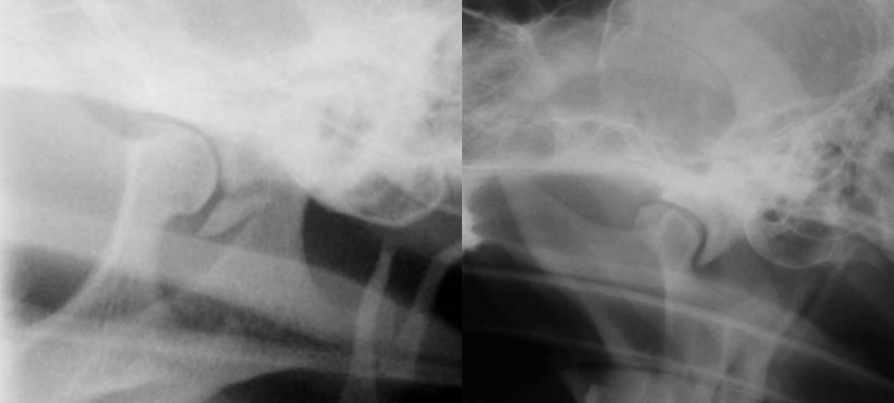

20

Q

identify pathology

A

left image: Fracture of retroauricular processus

right: TMJ dysplasia